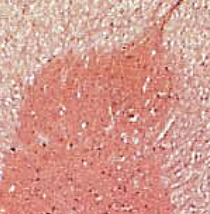

gray horns

what is the red butterfly called

anterior gray horns

lateral gray horns

posterior gray horns

central canal

A tiny channel found within the spinal cord and inferior medulla oblongata

gray commissure

connects masses of gray matter; encloses central canal